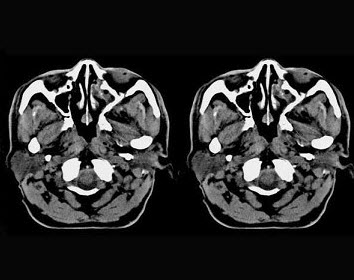

男,61岁,流鼻血三天。如图所示最可能的诊断为()。

A、鼻咽淋巴滤泡增生

B、鼻咽腺样体增生

C、鼻咽纤维血管瘤

D、小唾液腺瘤

E、鼻咽部息肉

正确答案:

A